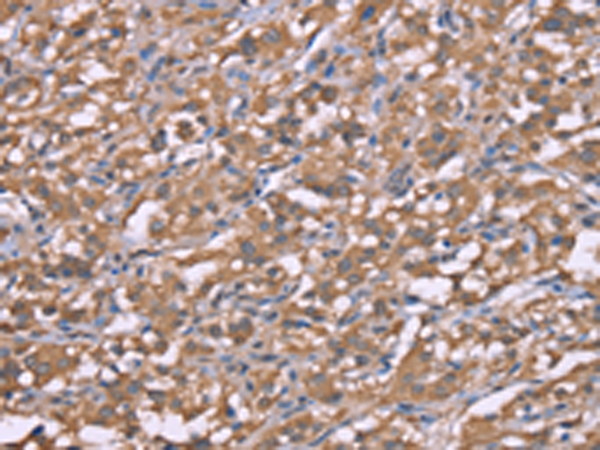

分类: 科研抗体货号: P04940别名: HRASLS2; PLAAT-2; PLA1/2-2应用: IHC反应种属: Human